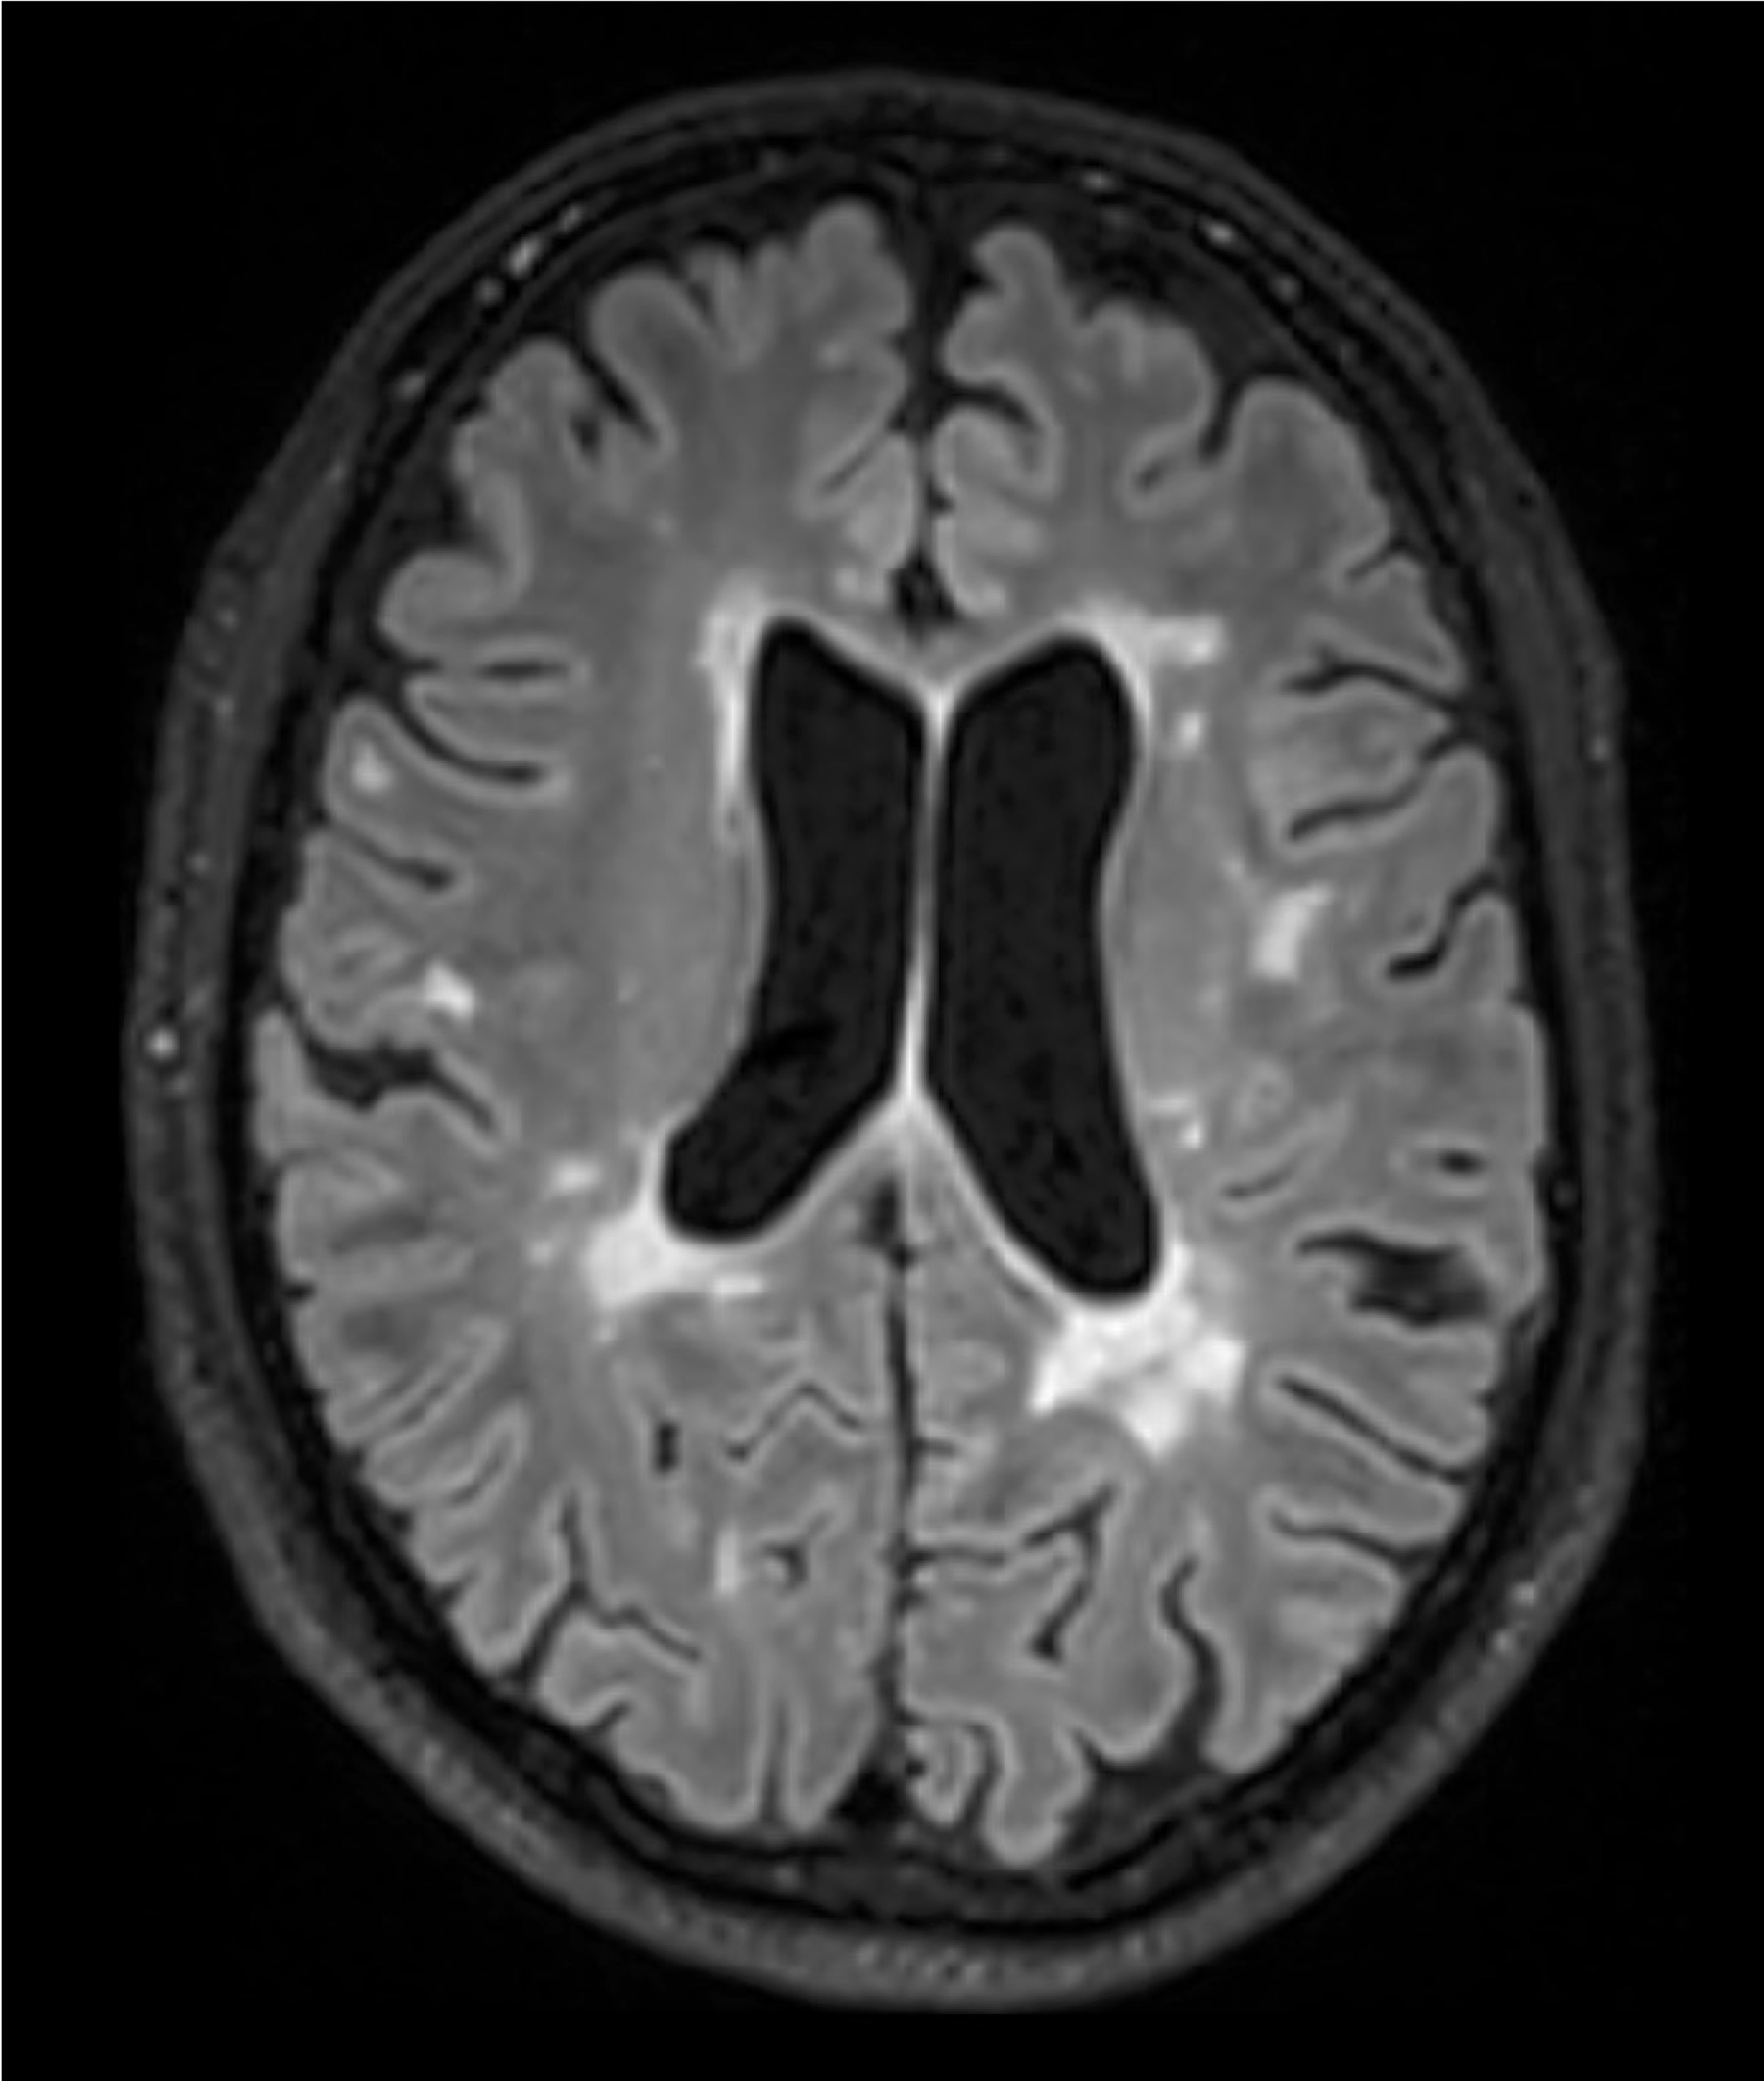

BU: Die Aufnahmen aus der Magnetresonanztomographie zeigen einen jungen Patienten mit Multipler Sklerose mit mehreren entzündlichen Läsionen des Gehirns. (© Radiologie Innsbruck)

Abseits klinischer Symptome, die von Einschränkungen des Sehvermögens bis hin zu Lähmungserscheinungen ein breites Spektrum umfassen, kann die Krankheitsaktivität bei MS auch bildgebend dargestellt werden. „Der Nachweis entzündlicher Läsionen im Gehirn mittels MRTerlaubt auch eine Einschätzung geringerer Krankheitsaktivität, denn vermeintlich stabile Patient:innen können trotz Therapie weiterhin neue, klinisch stumme, entzündliche Veränderungen entwickeln“, weiß Neuroimmunologe Harald Hegen, der an der Innsbrucker Univ.-Klinik für Neurologie bereits seit vielen Jahren zu MS forscht.

In die Studienkohorte wurden 131 MS-Patient:innen aus MS-Zentren in Österreich und der Schweiz eingeschlossen, die unter einer gering- bis moderat-effektiven Immuntherapie zwölf Monate lang klinisch stabil waren und dann einer MRT unterzogen wurden. „Wir konnten zeigen, dass Patient:innen mit schubförmiger MS, die unter Immuntherapie zwei oder mehr neue entzündliche MRT-Läsionen innerhalb eines Jahres entwickeln, auch bei klinischer Stabilität, also ohne Symptome, von einem Wechsel auf eine hoch-effektive Immuntherapie profitieren“, beschreibt Erstautor Gabriel Bsteh von der Medizinischen Universität Wien die zentrale Erkenntnis. Damit liefert die Studie eine für den klinischen Alltag wichtige Erkenntnis, die für die individuelle Therapieanpassung genutzt werden sollte.

„Nachdem Läsionen oft schon vor dem Auftreten klinischer Symptome in der MRT sichtbar sind, ermöglicht eine bildgebende Kontrolle bei Patient:innen mit einer gering- bis moderat-effektiven Therapie ein frühes Eingreifen in den individuellen Krankheitsverlauf“, betont Studienleiter Harald Hegen. In der Studienkohorte waren rund 40 Prozent der Patient:innen klinisch stabil, zeigten allerdings in der MRT schon eine oder mehrere Läsionen. Bislang war in der klinischen Praxis eine Therapieverstärkung nur nach Auftreten klinisch manifester Symptome angezeigt.